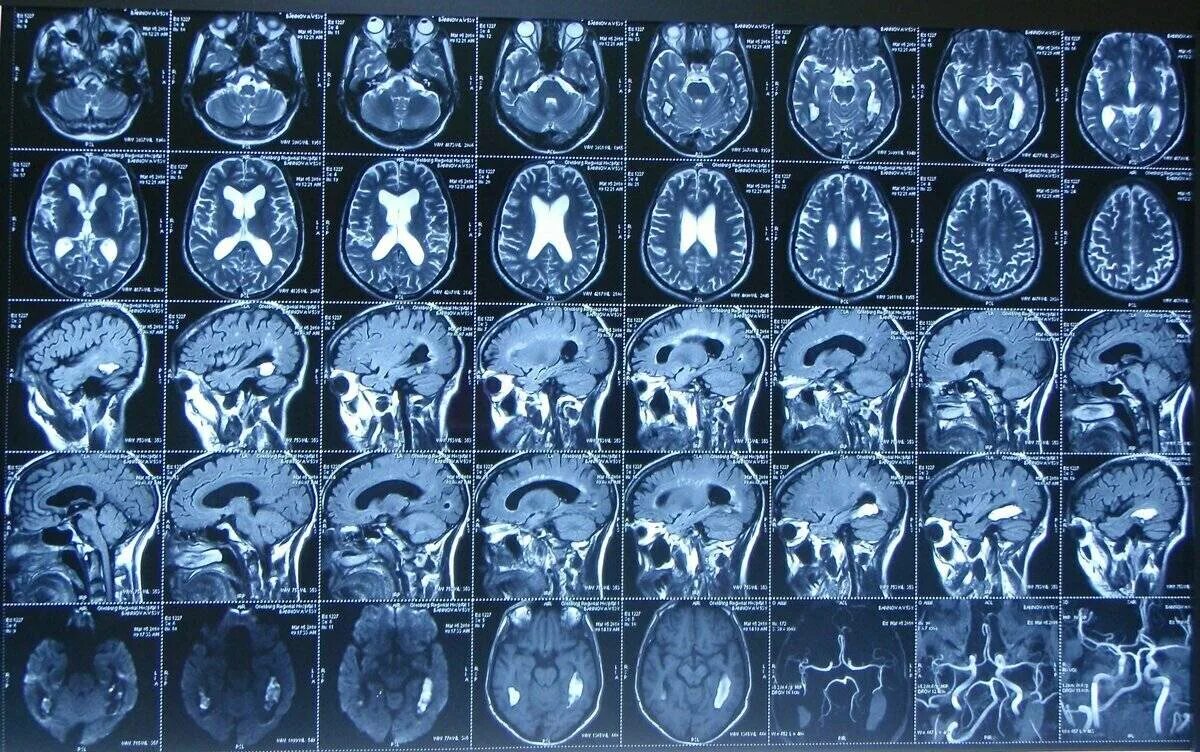

Кт пример